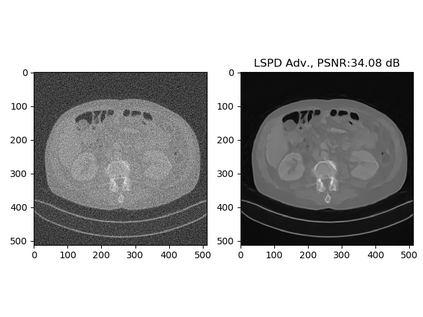

In this work we present a new type of efficient deep-unrolling networks for solving imaging inverse problems. Classical deep-unrolling methods require full forward operator and its adjoint across each layer, and hence can be computationally more expensive than other end-to-end methods such as FBP-ConvNet, especially in 3D image reconstruction tasks. We propose a stochastic (ordered-subsets) extension of the Learned Primal-Dual (LPD) which is the state-of-the-art unrolling network. In our unrolling network, we only use a subset of the forward and adjoint operator, to achieve computational efficiency. We consider 3 ways of training the proposed network to cope with different scenarios of the availability of the training data, including (1) supervised training on paired data, (2) unsupervised adversarial training which enable us to train the network without paired ground-truth data, (3) equivariant self-supervised training approach, which utilizes equivariant structure which is prevalent in many imaging applications, and only requires measurement data. Our numerical results demonstrate the effectiveness of our approach in X-ray CT imaging task, showing that our networks achieve similar reconstruction accuracies as the full-batch LPD, while require only a fraction of the computation.